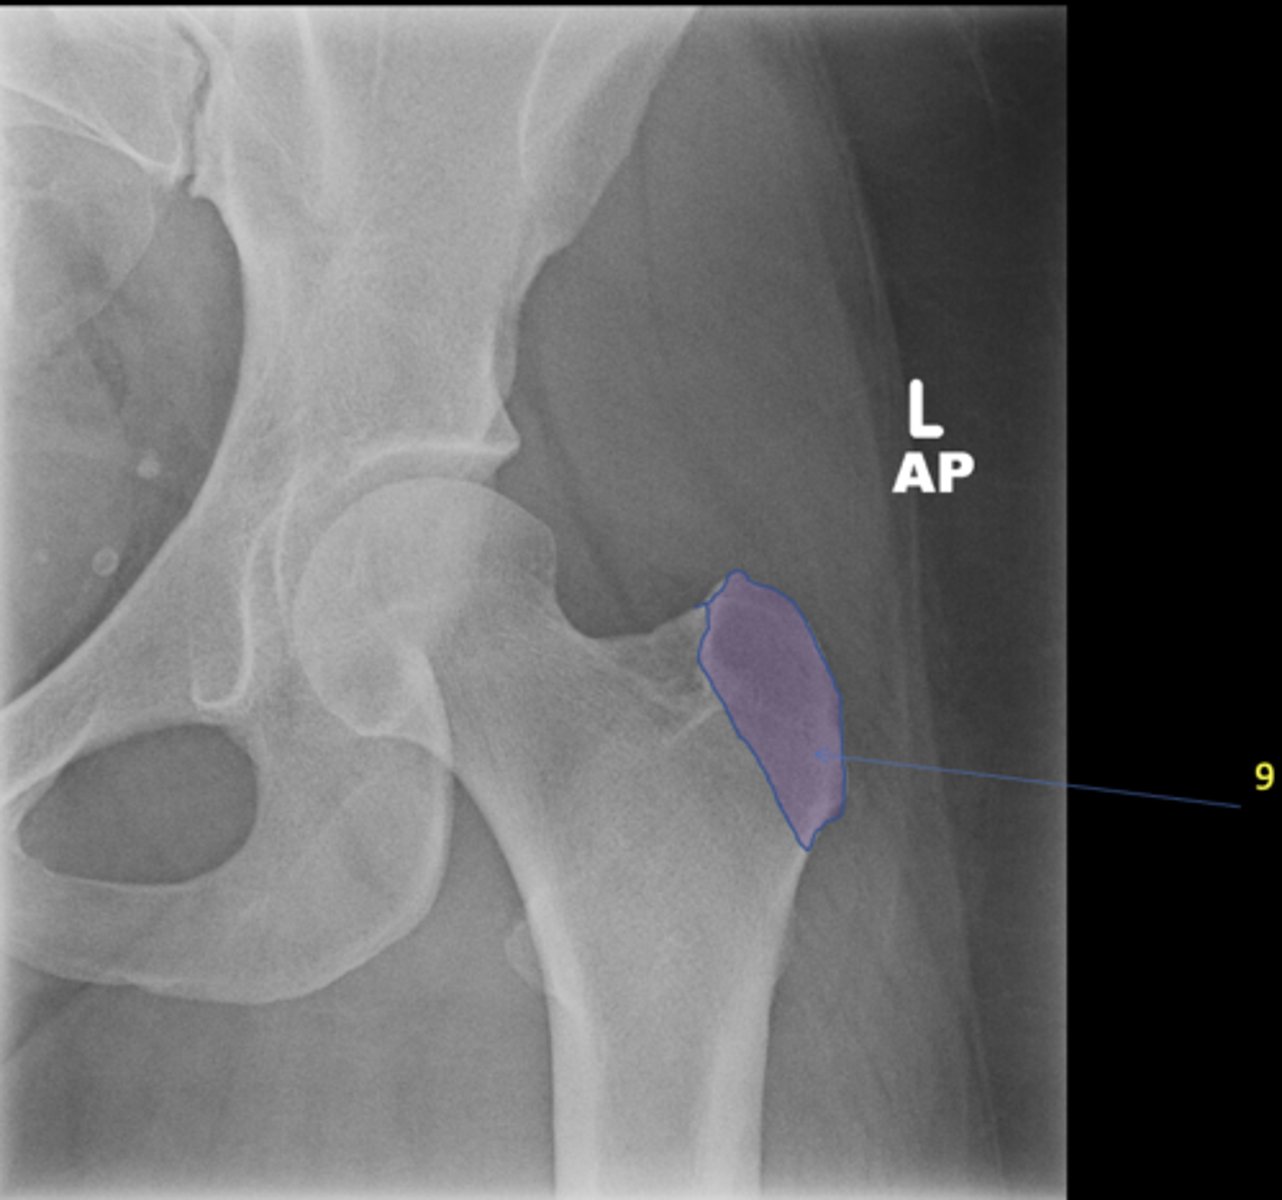

New cards

Left AP hip

View?

<p>View?</p>

29

Phleboliths

ID 1

<p>ID 1</p>

30

Obturator foramen

ID 2

<p>ID 2</p>

31

Kohler's teardrop

ID 3

<p>ID 3</p>

32

Gluteus medius

ID 4

<p>ID 4</p>

33

Ischial tuberosity

ID 5

<p>ID 5</p>

34

Acetabulum

ID 6

<p>ID 6</p>

35

Anterior inferior iliac spine

ID 8

<p>ID 8</p>

36

Lesser trochanter

37

Greater trochanter

ID 9

<p>ID 9</p>

38

Sacroiliac joint

ID 10 (joint)

<p>ID 10 (joint)</p>

39

Sacrum

ID 11 (bone)

<p>ID 11 (bone)</p>

40

ID 12

<p>ID 12</p>

41

Anterior superior iliac spine

ID 13

<p>ID 13</p>